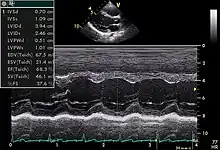

Echocardiogram in the parasternal long-axis view, showing a measurement of the heart's left ventricle

Motion mode is infrequently used in modern echocardiography. It has specific uses and has the benefit of very high temporal fidelity (e.g., measuring LV size at end diastole).